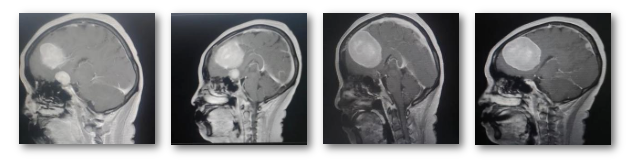

入院后,为更准确诊断病情和制定最佳治疗方案,神经外科二病区主任白西民及团队根据影像学资料、病史、查体分析诊断:左额部窦镰旁及鞍结节多发占位,较大者大小约6.0*5.3*5.7cm,与周围神经血管粘连紧密,考虑为脑膜瘤可能,且肿瘤巨大,需尽快手术治疗。经过多次研讨,与家属充分沟通,科室为吴女士制定详细周密手术方案。

术中,经过初步探查发现,手术比想象得更难,医生面临的考验,不仅要切除肿瘤,还要尽可能保护血管及神经功能。白西民带领团队在手术显微镜下沉着应对,先切断肿瘤的血液供应控制出血,分块切除肿瘤,凭借精湛手术技巧和丰富临床经验对肿瘤进行精细剥离,仔细保护与肿瘤粘连紧密的重要神经、血管结构。

手术从上午08:40一直持续到晚上20:05分,经过近12个小时的“刀尖惊魂”,凭借精湛手术技巧和丰富临床经验,不仅顺利将肿瘤完整剥离,而且完整保留了神经功能,手术取得圆满成功。